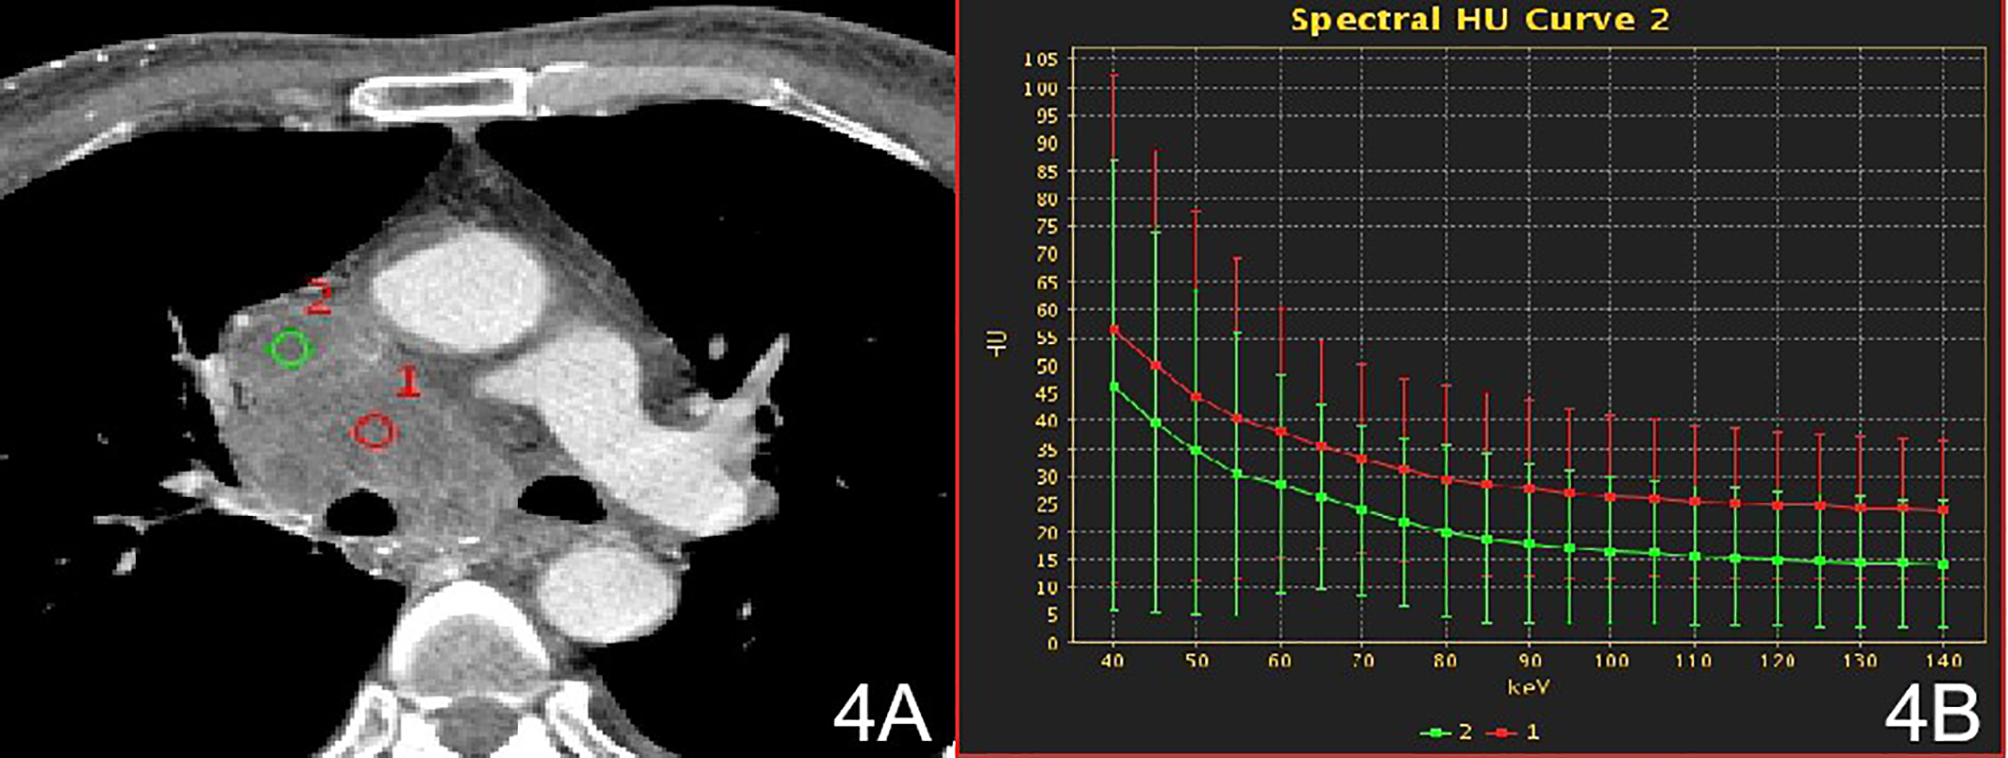

Figure 4

Stage IV, (A) 70 keV single-energy CT value of the arterial phase is used to outline the ROI of the lesion; (B) Arterial lesion spectrum (red), intravascular emboli spectrum (green).

There were no significant differences in the slopes of the energy spectrum curves for stage IV lesions, metastatic lymph nodes, and intravascular emboli (P > 0.05) (Table 4) (Figures 3 and 4).The slope of the energy spectrum curve combined with the energy spectrum curve graph, the accuracy of assessing lymph node metastasis and embolic properties is 80.0%.

The 54 patients evaluated in this study included 19 with stage I, 15 with stage II, 8 with stage III lesions, and 12 with stage IV lesions according to the Masaoka-Koga staging. The 54 patients were divided into three groups: non-invasive group (stage I), invasive surrounding fat group (stage II), and invasive surrounding structures (pleura, pericardium, lung, blood vessels) and distant metastasis group (stages III and IV). In the qualitative diagnosis, irregular or lobed edges lesions on conventional CT. It may indicate that the tumor capsule and extracapsular fat have been invaded (25). In this study, ROIs were delineated in stage I and stage II solid lesions, extracapsular fat, and anterior chest wall fat. The energy spectrum curves for the lesion, extracapsular fat, and anterior chest wall fat were obtained. In stage I lesions, the energy spectrum curve of the tumor parenchyma and the energy spectrum curve of the extracapsular fat have the opposite shape, and the energy spectrum curve of the extracapsular fat and the front chest wall fat have the same shape, indicating that the lesion did not extend outside the capsule. The slope of the spectrum curve for the anterior chest wall fat in stage II lesions showed statistically significant differences with those of the spectra for the lesion and the lesion’s extracapsular fat, indicating that the lesion had invaded the extracapsular fat. According to the spectrum curve, the lesion and the fat in the outer capsule of the lesion were homologous. In this study, ROIs were delineated in pathologically confirmed mediastinal lymph node with metastasis, intravascular tumor emboli, and solid lesions. The spectral curves for the metastatic lymph nodes, intravascular emboli, and lesions were consistent and the differences in the slopes were not statistically significant, indicating that the lesions were homologous to lymph nodes and intravascular emboli (26). Among these parameters, the energy spectrum curve objectively reflects whether the tumor parenchyma and extracapsular fat are homologous, and whether the enlarged lymph nodes and emboli are metastatic.